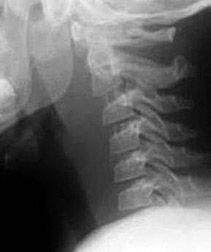

C3 vertebral body - Copyright – Stock Photo / Register Mark Figure 3: Anterior wedging of the C3 vertebral body; a normal finding in the pediatric spine. Absence of Lordosis: The absence of lordosis, although potentially pathologic in an adult, can be seen in children up to 16 years of age when the neck is in a neutral position. The normal posterior intraspinous distance is a good indicator of ligamentous integrity and should not be more than 1.5 times greater than the intraspinous distance one level either above or below the level in question. In children, the flexion maneuver can increase the distance between the tips of the C1 and C2 spinous processes. This widened C1-2 intervertebral distance is a normal finding and should not be misinterpreted as ligamentous injury. This finding is postulated to be secondary to the tight ligamentous attachment between the skull base and C1.

Pediatric C spine - Copyright – Stock Photo / Register Mark Figure 4: Pediatric C spine in expiration phase of respiration. The following are some of the more common variations: The posterior arch of C1 can remain cartilaginous. The apical odontoid epiphyses can remain visualized in children up to 8 years of age. In general, anterior wedging up to 3 mm of the vertebral bodies can be present until the endplates are fused and should not be confused with a compression fracture. C3 seems to demonstrate the most profound appearance of anterior wedging when present. (Figure 3)